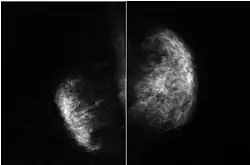

| Missing right breast and right pectoralis major muscle in Poland syndrome[2] | |

Poland syndrome is a birth defect characterized by an underdeveloped chest muscle and short webbed fingers on one side of the body.[3][1] There may also be short ribs, less fat, and breast and nipple abnormalities on the same side of the body.[1] Typically, the right side is involved.[3] Those affected generally have normal movement and health.[1]

Poland syndrome is sometimes diagnosed at birth, based upon the physical characteristics. Imaging techniques such as a CT scan may reveal the extent to which the muscles are affected.[9] The syndrome varies in severity and as such is often not reported until puberty, when lopsided growth becomes apparent.[10]

The implant replaces the pectoralis major muscle, thus enabling the thorax to be symmetrical and, in women, the breast as well. For females affected by Poland syndrome, breast reconstruction is a key aspect of treatment, and latissimus dorsi muscle transfer offers a reconstructive option.